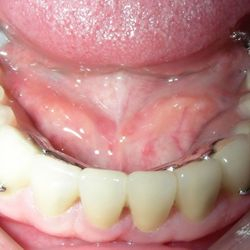

Η ασθενής της φωτογραφίας (65 ετών) προσήλθε στο ιατρείο παραπονούμενη για δυσκολία στη μάσηση. Ηταν επίσης δυσαρεστημένη με την όψη που είχαν τα φυσικά της δόντια.

Είχε επί χρόνια παραμελήσει την στοματική της υγεία με αποτέλεσμα πολλαπλές εξαγωγές των πίσω δοντιών της και φθορά των μπροστινών.

Το στόμα της αποκαταστάθηκε με μεταλλοκεραμικές στεφάνες και γέφυρες στα άνω δόντια και στα κάτω πρόσθια, ενώ στην κάτω γνάθο τοποθετήθηκε επίσης μια μερική οδοντοστοιχεία με άγκιστρα.

Μετά το πέρας της θεραπείας, η όψη του στόματος είχε βελτιωθεί δραματικά και η ίδια ανέφερε οτι πλέον μπορούσε να μασήσει όλες τις τροφές χωρίς περιορισμούς.